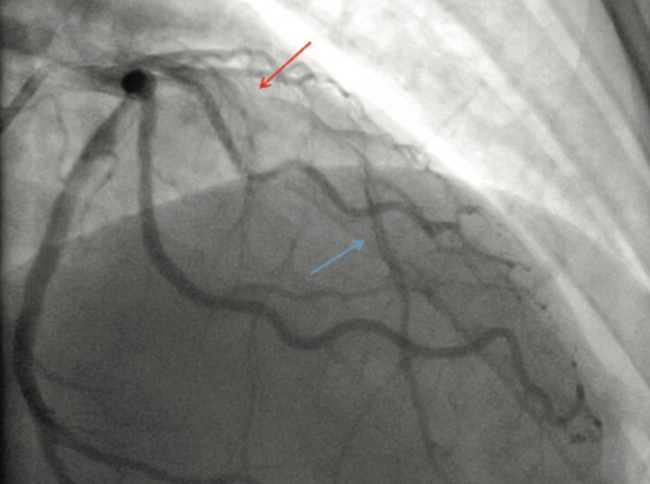

Spontaneous coronary artery dissection (SCAD) is a rare cause of acute coronary syndrome. Intravascular imaging with intravascular ultrasound (IVUS) has a pivotal role in the diagnosis and management of SCAD. IVUS is used to identify the extension of the intramural hematoma, examine intimal tears, and differentiate the true and false lumen. We present a case in which the diagnosis of SCAD to the distal left anterior descending artery was ambiguous on coronary angiography, with subsequent IVUS imaging demonstrating the correct pathology.